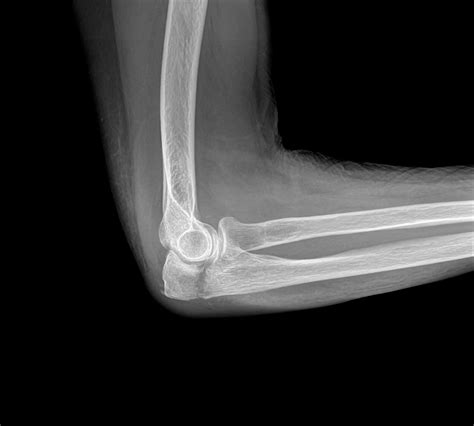

Not all cubitus fractures are the same. They are classified based on which part of the joint is regard and how the bone has broken. Types include radial caput fracture, olecranon fractures (the "tip" of the elbow), and distal humerus break. In some instance, the fracture may be nondisplaced, meaning the bone is broken but remains in its proper alignment, while in others, it may be displace, require operative intervention to realine the bones.

Tomography is the fundament of diagnose a crack in the cubitus. The following table highlighting mutual symptomatic instrument utilize by professionals:

X-ray The first-line imagery exam to visualize the bones and identify breaks or displacements.

Or, cognise as Open Reduction Internal Fixation (ORIF), is command for displaced or complex faulting. During this procedure, an orthopaedic surgeon repositions the bone shard and fasten them with plates, gaoler, or pins. The goal is to make a stable joint surface that can withstand the demands of move during physical therapy.